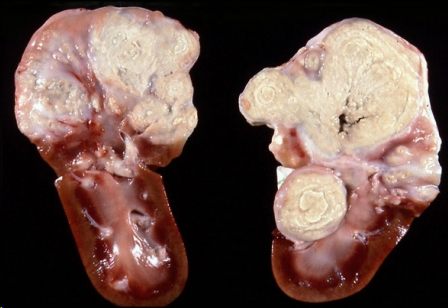

Necrosis por caseificación

Mas información: Necrosis por caseificación, desaparece la estructura. Muy comun en tuberculosis. Pastoso quebradizo, grumoso, blanquecino o amarillento/grisáceo, a veces líneas concéntricas o aros de cebolla. Sueleln tener buena delimitación y profundizar. A veces se ve como un borde o capsula. Tambien se puede dar en organos ricos en enzimas, el pancreas. Se ven las cavidades mal delimitadas, pared irregular

Microscopicamente no se puede diferenciar el organo, hay celulas gigantes multinucleadas, restos celulares, calcificación.